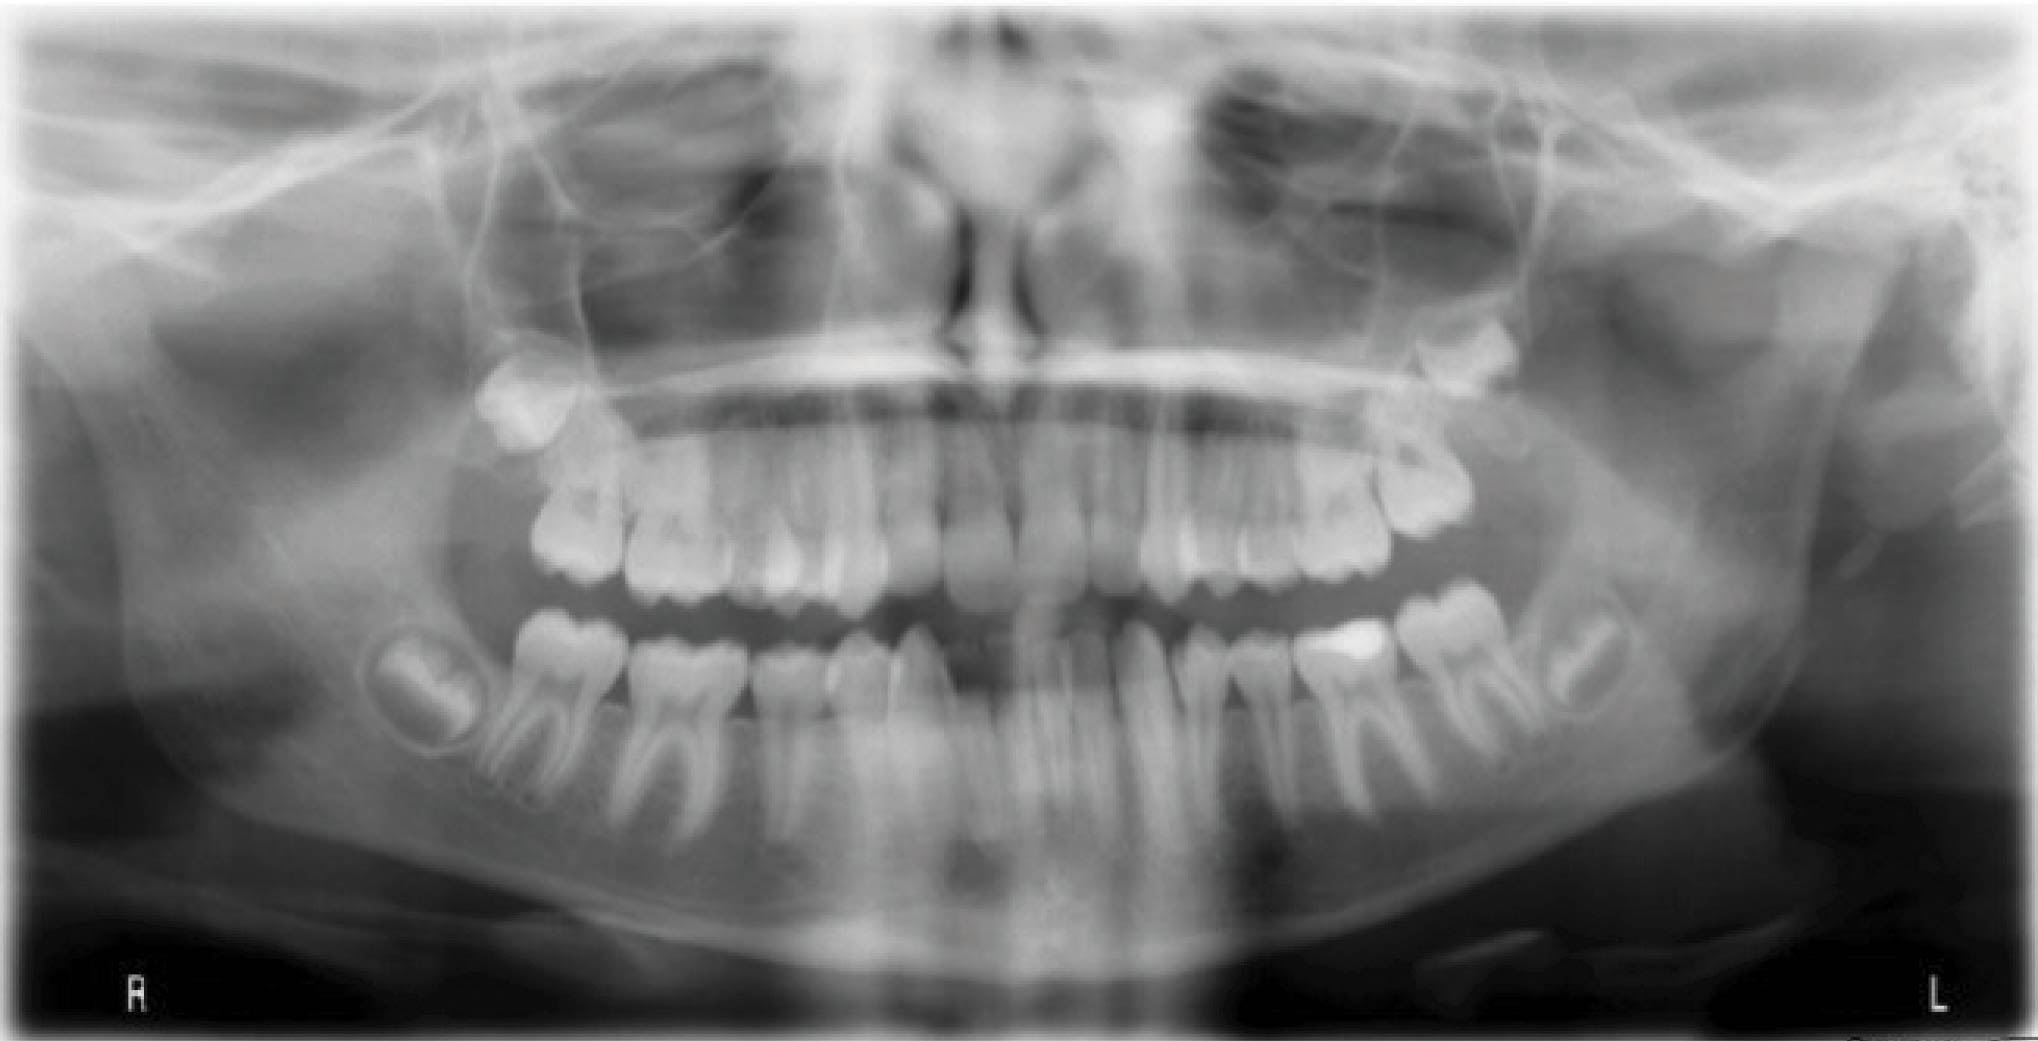

بیمار دارای اکلوژن کلاسIII با کرادینگ مختصر در هر دو فک است (شکلهای 121-۶ الی 123-۶). قرار بود که هم درمان ارتودنسی و هم درمان جراحی برای بیمار انجام شود. چون بیمار تمایلی به جراحی نداشت، لذا به راههای غیرجراحی بیشتر فکر کردیم. بخاطر شدت ناهنجاری در بُعد افقی تصمیم به کشیدن دو پرمولر پایین و استفاده از الاینر شفاف گرفتیم.

شکل 121-6

شکل 122-6

شکل 123-6

به این نتیجه رسیدیم که فک بالا را غیرکشیدنی به کمک اکسپنشن خلفی و استریپ دندانها درمان کنیم. در فک پایین هم با کشیدن ۴های پایین فضای کافی برای رفع کرادینگ و اصلاح اورجت بدست میآوریم.

پیشرفت درمان را در (شکل 124-۶) مشاهده میکنید. در این مرحله، مزیالی نمودن مولر دوم شروع میشود.

شکل 124-6

در انتهای درمان (شکل 125-۶) در قوس پایین تمام فضاها بسته شدهاند. رابطه کانینی کلاسI گردید. رابطه مولری نیز یک کاسپ کامل کلاسIII است. نتایج بدست آمده برای یک درمان غیرجراحی بسیار عالی شده است. عکس OPG پایان کار (شکل 126-۶) ریشههای موازی را نشان میدهد.

شکل 125-6

شکل 126-6